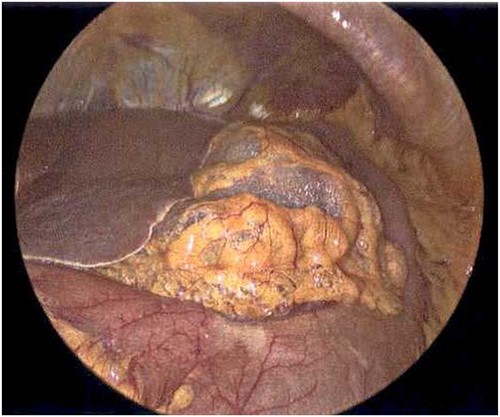

On Hospital Day 2, an interval CXR showed continued resolution of the right-sided pneumothorax but worsening subcutaneous emphysema of the bilateral chest wall and pneumoperitoneum (Fig. 3). Surgical consultation was sought, leading to diagnostic laparoscopy. In the abdomen, emphysematous changes within the gastrohepatic ligament and omental adhesions to the anterior abdominal wall were visualized (Figs 5 and 6). Laparoscopic exploration revealed no diaphragmatic injury or perforated viscera but identified emphysematous changes throughout the preperitoneal space, small and large bowel mesentery, and right paracolic gutter (Figs 7 and 8). Immediate post-op CXR no longer showed evidence of pneumoperitoneum (Fig. 4). The patient was transferred back to the ICU and extubated after three days on Day 5. After the removal of chest tube and transfer to a medical floor on Day 8, the patient developed aspiration pneumonia that was treated with antibiotics. She was discharged on Day 15.

Laparoscope revealing emphysematous changes within the gastrohepatic ligament.